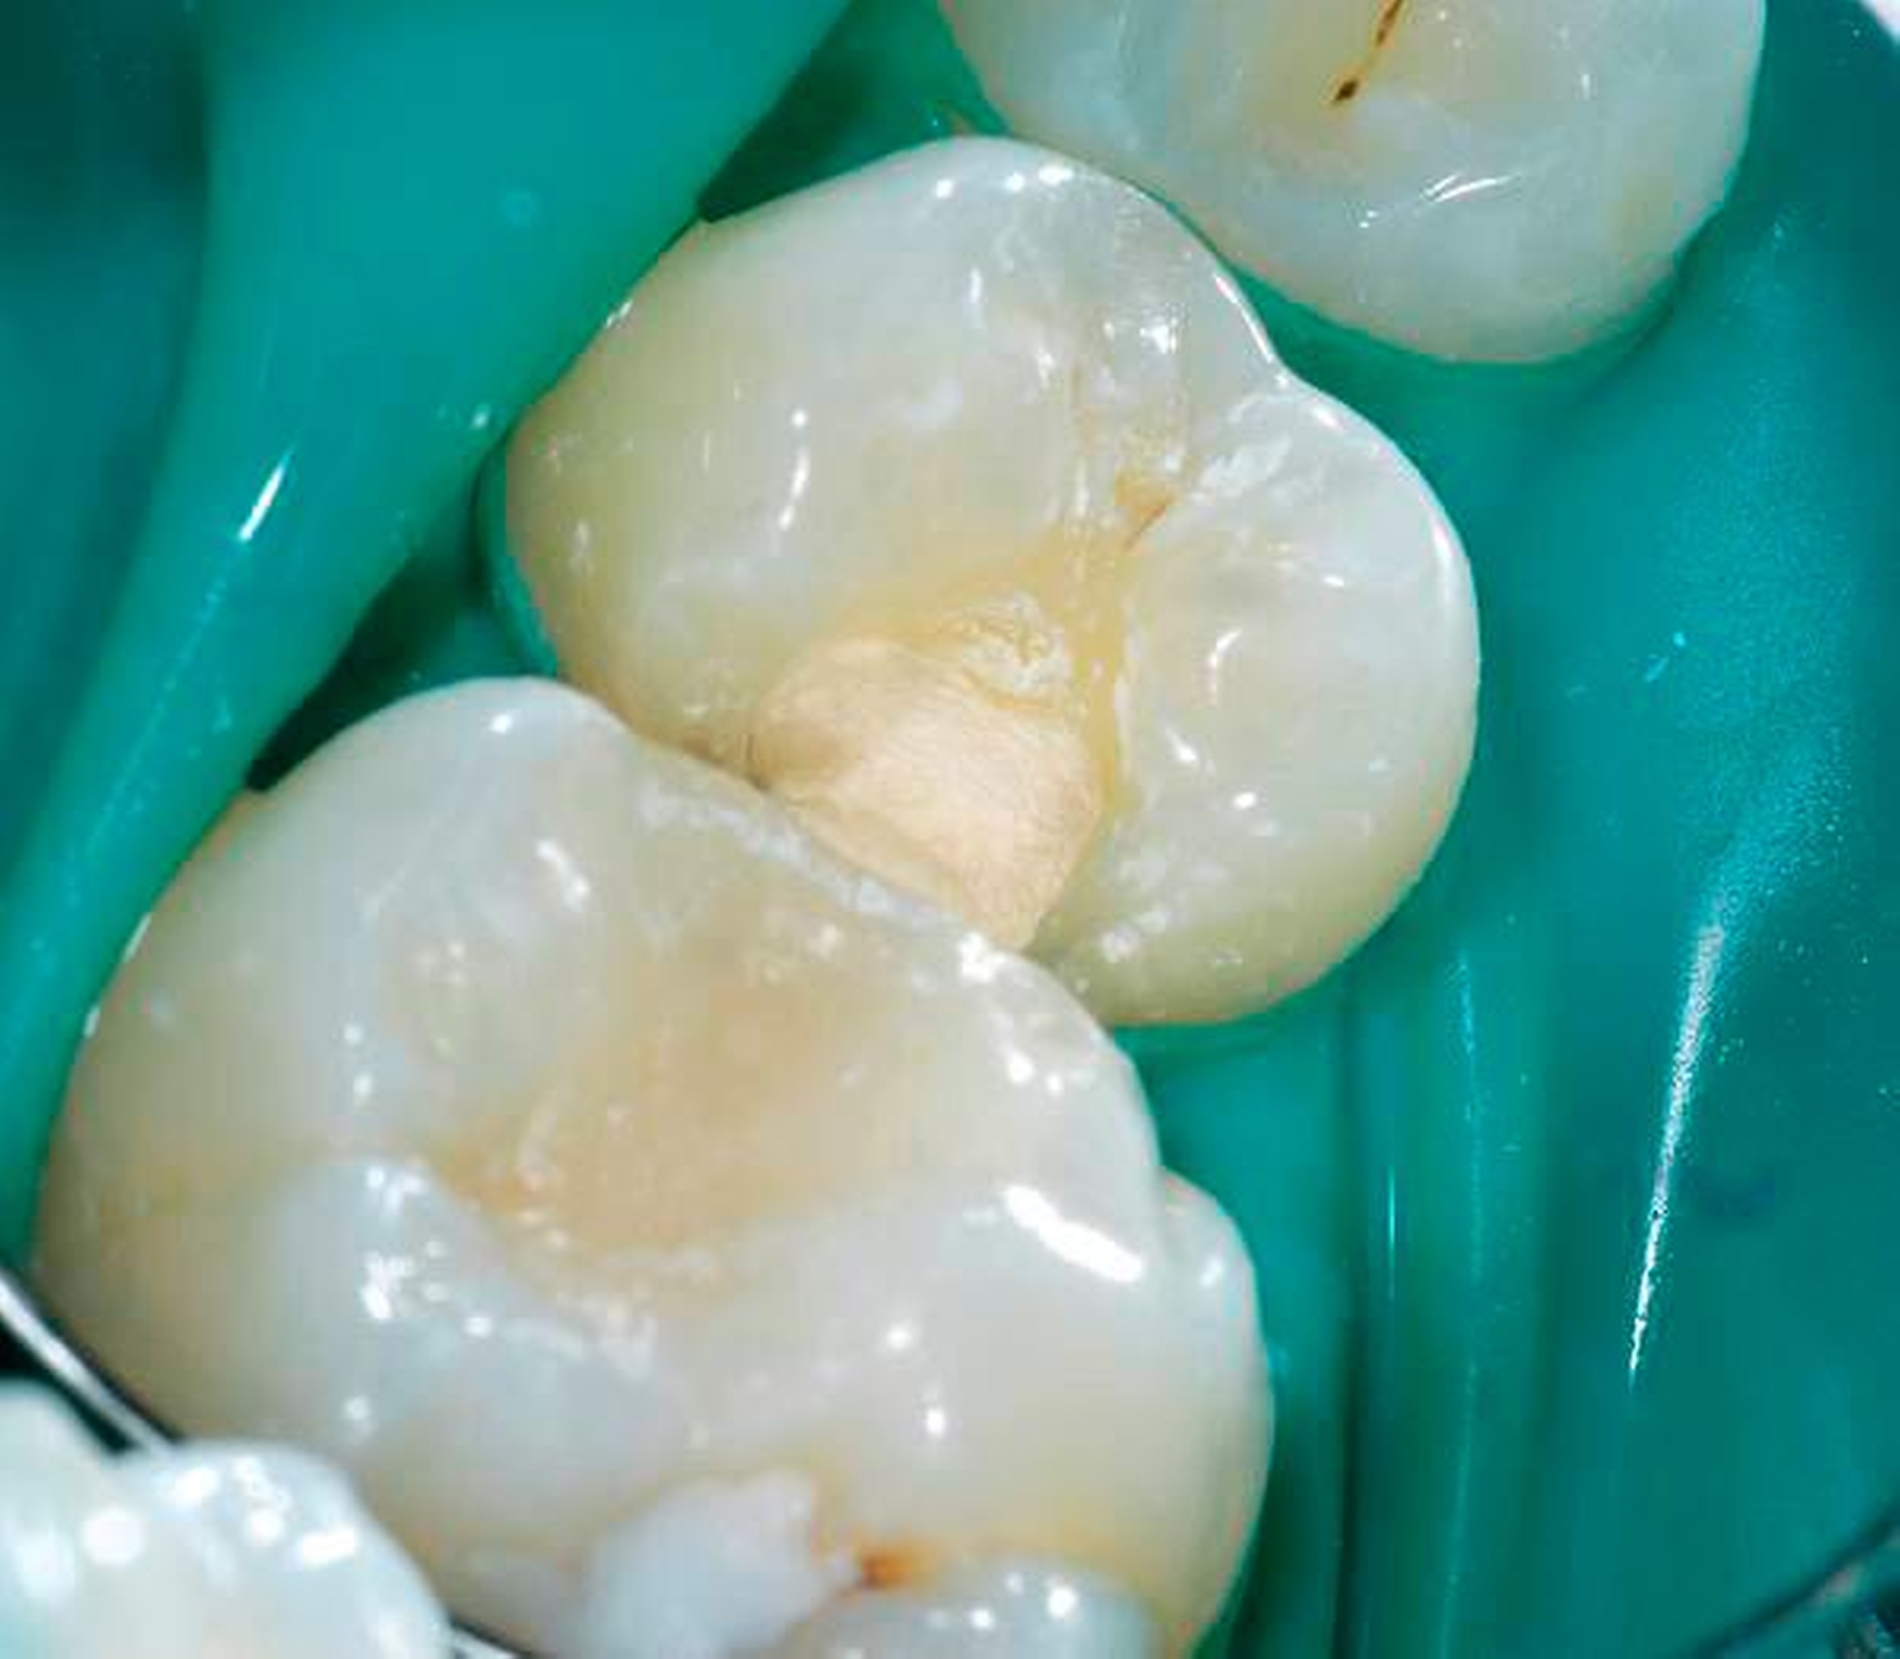

Im Gegensatz zu Reaktionsdentin wird Reparaturdentin definiert als Tertiärdentin, dessen Matrix nach dem Untergang der primären postmitotischen Odontoblasten als Reaktion auf einen Reiz hin gebildet wird [59, 90, 91]. Die Bildung von Reparaturdentin ist dabei unter biologischen Gesichtspunkten sehr viel komplexer als die von Reaktionsdentin, da in Fällen einer ausgeprägteren Verletzung der Pulpa, zum Beispiel nach mechanischer Pulpafreilegung, der primäre Odontoblast zerstört wird. Wie bereits ausgeführt, ist aber ohne Odontoblasten eine physiologische Dentinbildung nicht möglich. Trotzdem kommt es nach direkter Überkappung einer gesunden, nicht-entzündeten Pulpa zu einem hartgewebigen Verschluss der Eröffnungsstelle. Dieses Reparaturdentin ist ein sehr heterogenes, amorphes, atubuläres, mineralisiertes Gewebe und unterscheidet sich daher histologisch von Primär- und Sekundärdentin, aber auch von Reaktionsdentin. Reparaturdentin ist knochenähnlich und wird daher auch als Fibrodentin oder Osteodentin bezeichnet [36, 37] (Abbildungen 1 und 2). Es ist daher fraglich, ob man hier von einer Dentinbrücke reden kann, da es sich unter histologischem Aspekt nicht um Dentin handelt. Sollte es sich bei Reparaturdentin wirklich um eine Bildung neuen Dentins handeln, würde dies bedeuten, dass ein neuer Typ Zellen den zerstörten primären Odontoblasten ersetzen würde. Woher diese Ersatzzellen allerdings stammen sollen, ist auch bisher völlig ungeklärt [81]. Es gibt dazu verschiedene Theorien: Zum einen vermutet man, dass bei der Zahnbildung während der letzten Zellteilung des Prä-Odontoblasten vor der terminalen Differenzierung eine der Tochterzellen an der dentalen Basalmembran positioniert wird und dort dann das induktive Signal erhält, sich zu einem Odontoblasten zu differenzieren. Die andere Tochterzelle wandert in die sogenannte Höhlzellschicht der Pulpa und dient möglicherweise als Progenitorzelle („Vorläuferzelle“) zur Bildung von Odontoblasten-ähnlichen Zellen während der tertiären Dentinogenese [35–37, 59, 82, 91]. Bisher gibt es keinen Nachweis, dass sich Zellen aus der Höhlzellschicht zu einem sekundären Odontoblasten (Ersatzodontoblasten) differenzieren. Es gibt aber Autoren, die dies dennoch für wahrscheinlich halten. Zumindest scheinen Höhlzellen den geschädigten primären Odontoblasten in seiner Funktion zu unterstützen [36, 37].

Nachgewiesenermaßen können Calciumsilikat-Zemente die Pulpa zur Bildung von Hartgewebe (Tertiärdentin) stimulieren und sind daher für die Versorgung tiefer kariöser Defekte nach Exkavation und somit für die Vitalerhaltung der Pulpa sehr gut geeignet [15, 21]. Nach indirekter Überkappung mit Biodentine kommt es reproduzierbar zur Ausheilung einer reversiblen Pulpitis [45]. Auch wenn mehr klinische Langzeitstudien zur Vitalerhaltung der Pulpa mit Calciumsilikat-Zementen wünschenswert sind, scheinen nach bisheriger Datenlage Calciumsilikat-Zemente für die indirekte Überkappung der Pulpa besser geeignet zu sein als Calciumhydroxid [2]. Für die direkte Überkappung wurde nachgewiesen, dass Calciumsilikat-Zemente zu besseren klinischen Ergebnissen und höheren Erfolgsraten führt als Calciumhydroxid [50, 60, 63]. Hinsichtlich der Hartgewebebildung ist es dabei unerheblich, ob man ein MTA-Zement oder Biodentine verwendet. Beide Arten von Calciumsilikat-Zement führen beim Menschen zu einer identischen Hartgewebsbrückenbildung [68] (Abbildungen 3 bis 10).